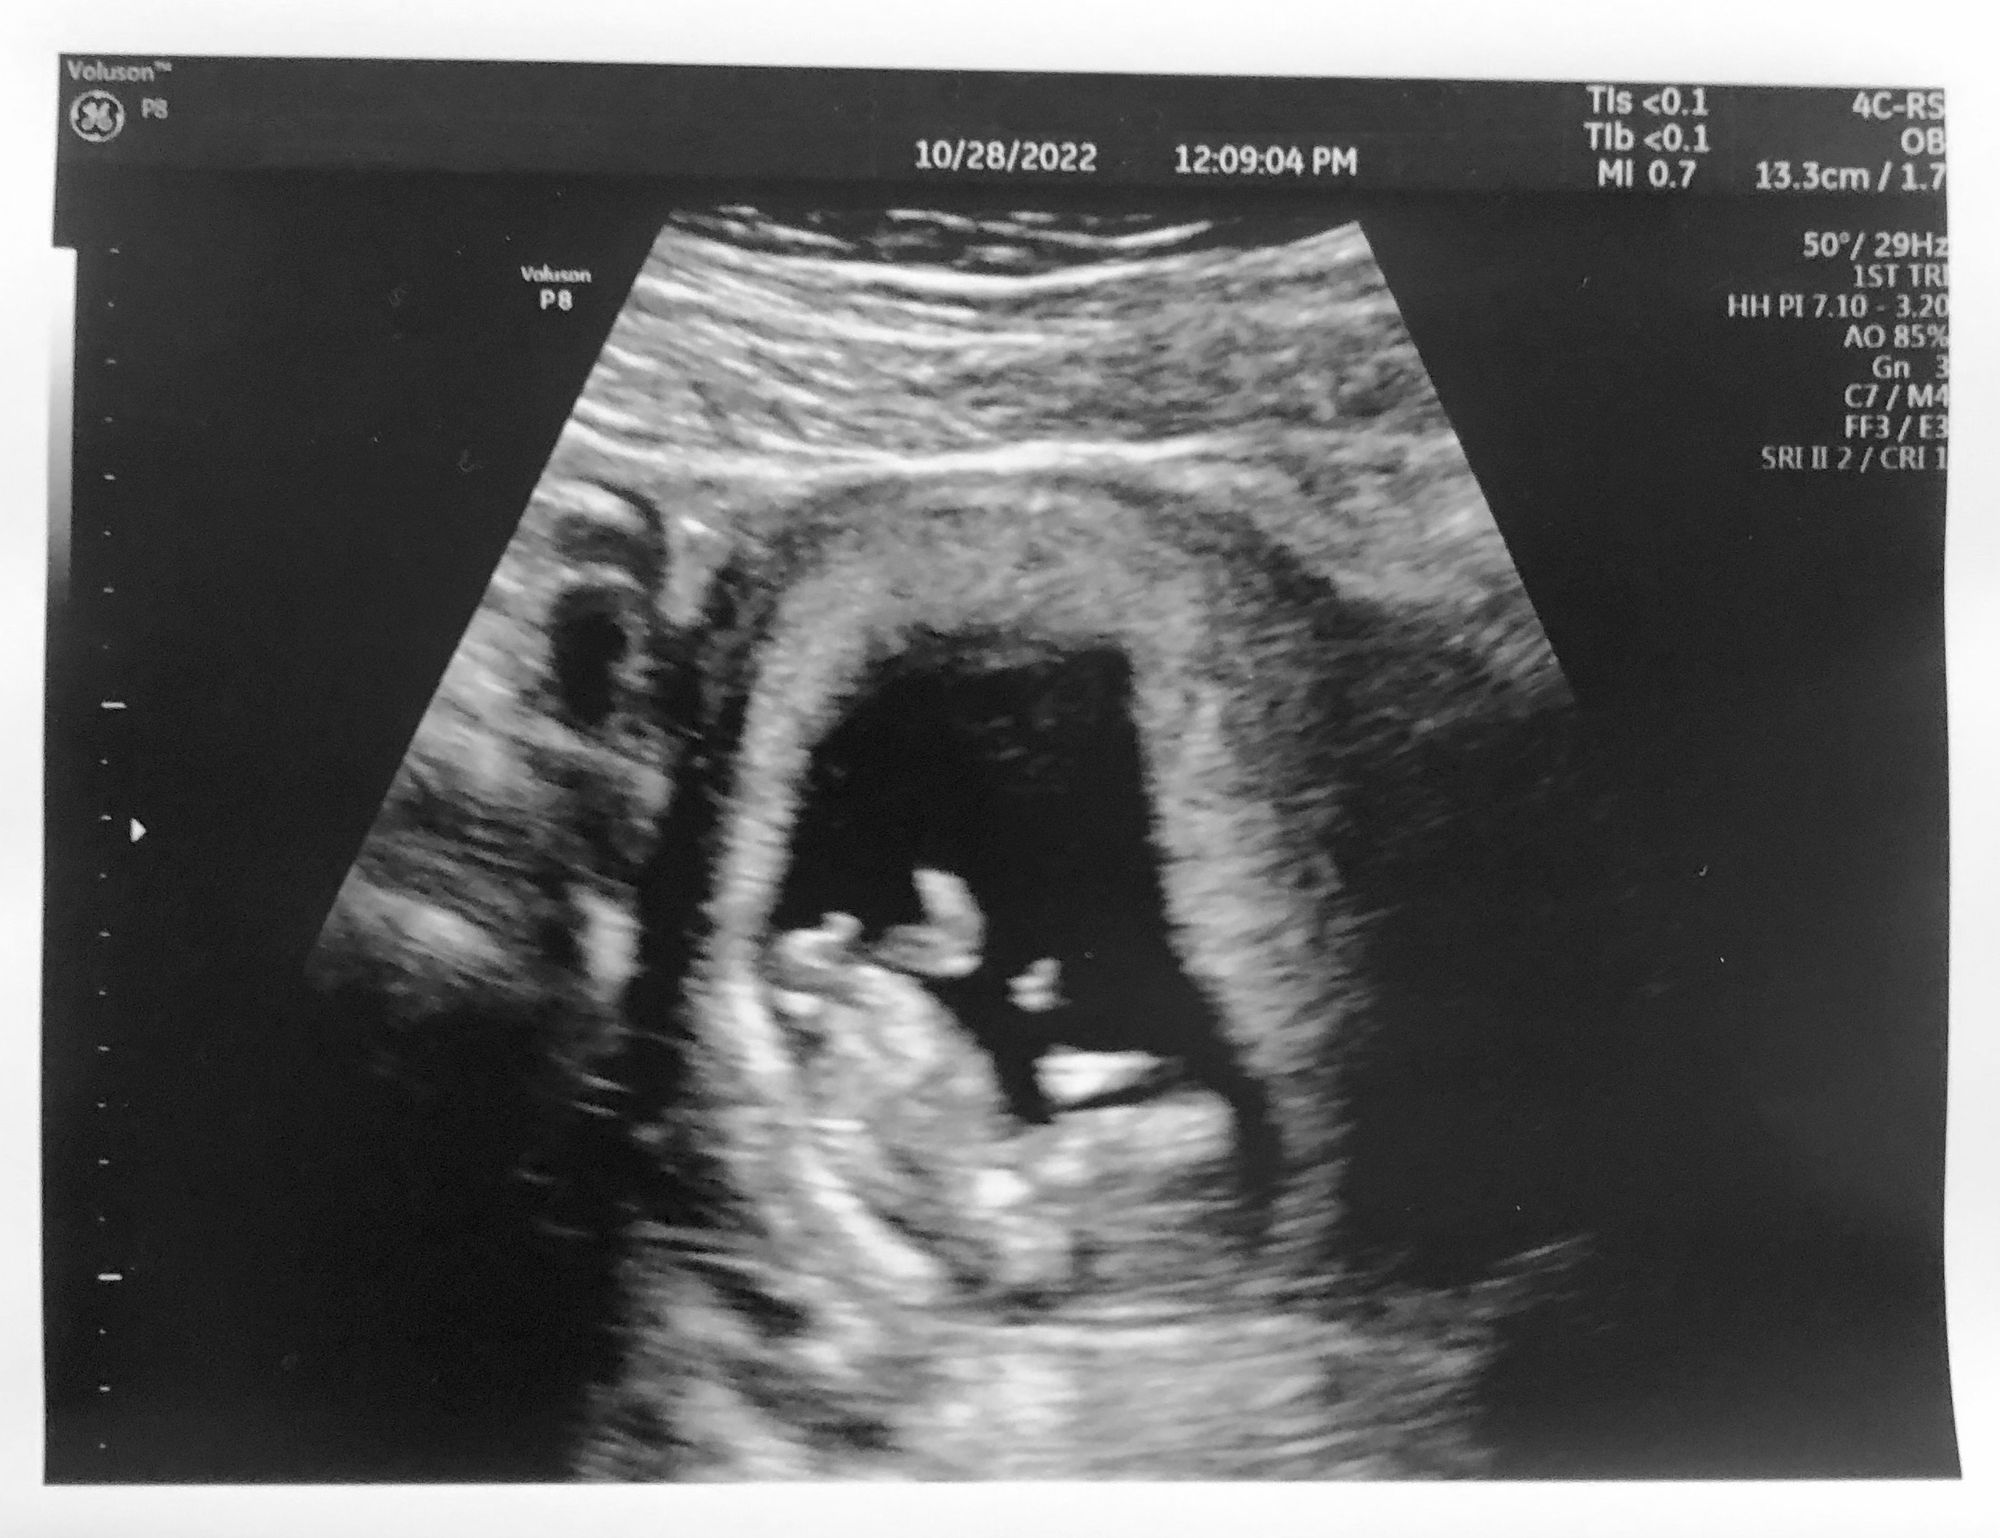

Guess what: I'm pregnant. A baby is growing inside my abdomen. My uterus has more than doubled in size and produced an entire new organ, the placenta. Plus my child's organs, sketches in miniature — the heart has been fluttering for more than a month! We saw it on the first ultrasound. Then today at the 12-week ultrasound, kicking legs.